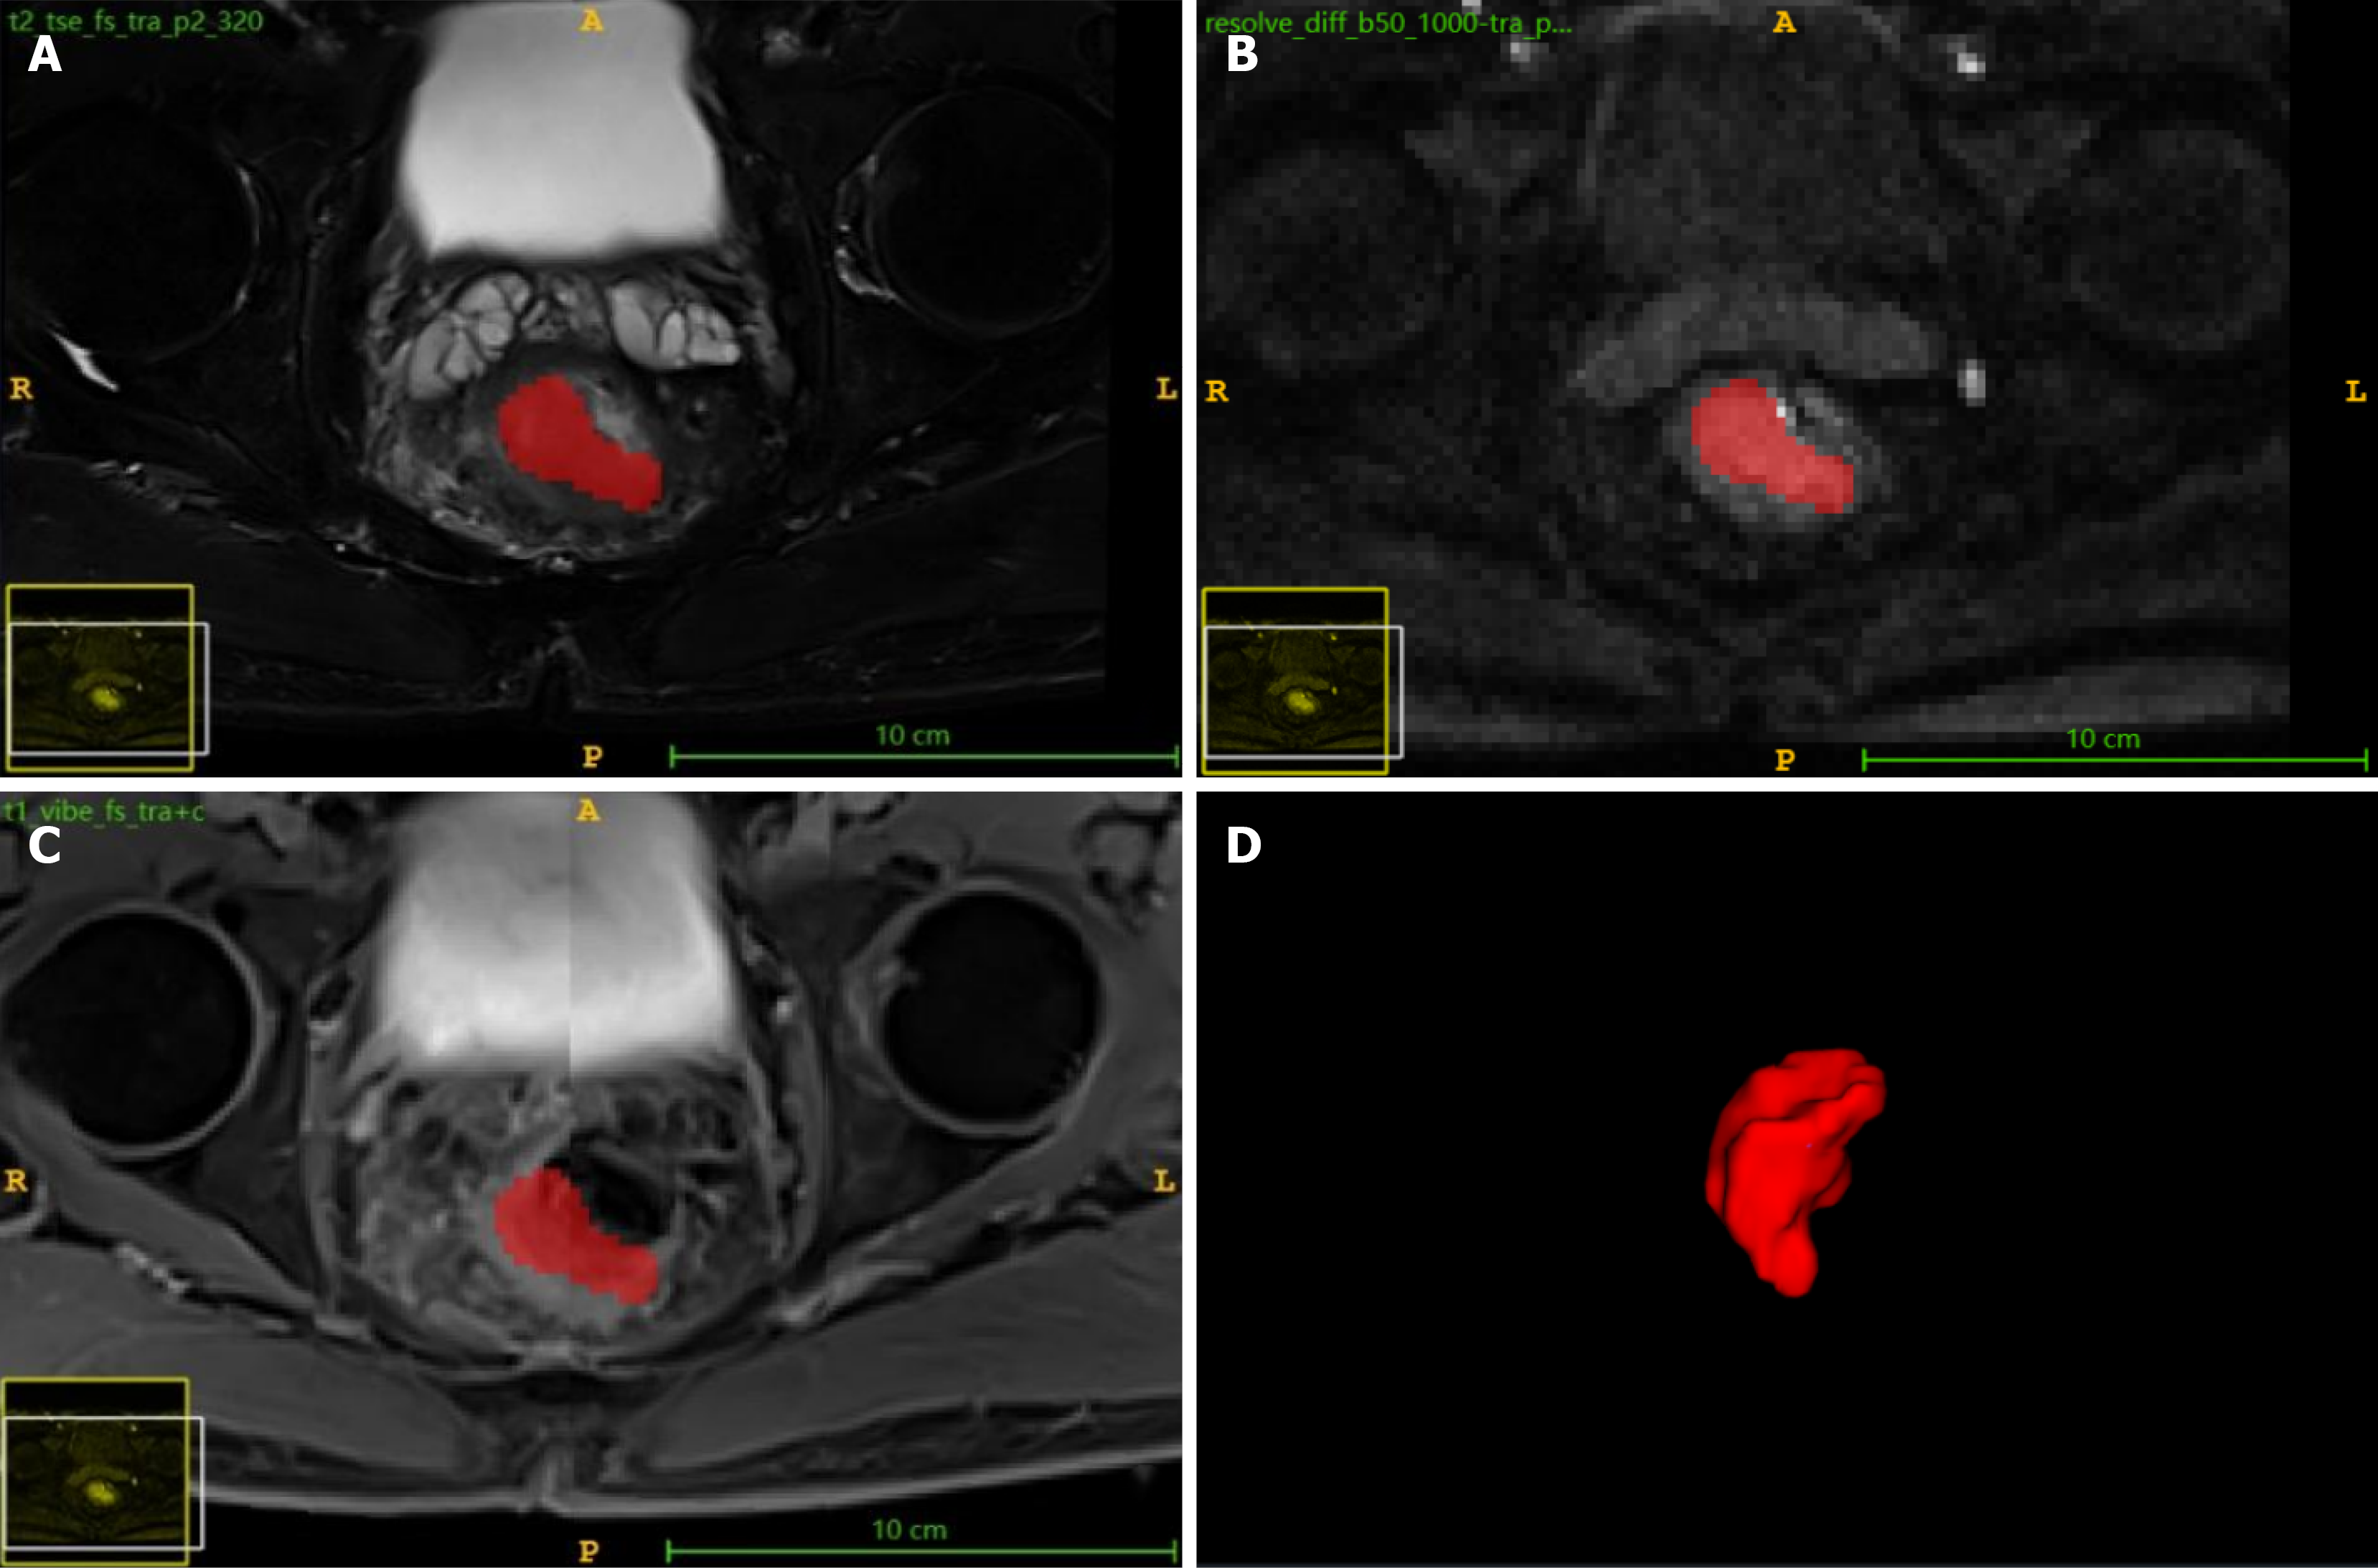

Figure 1 Region of interest delineation of rectal cancer lesion area.

A: Region of interest (ROI) delineation on axial fat-suppressed T2-weighted imaging; B: ROI delineation on diffusion-weighted imaging; C: ROI delineation on axial fat-suppressed T1-weighted contrast-enhanced imaging; D: Volume of rectal cancer region of interest based on single-slice ROI fusion.